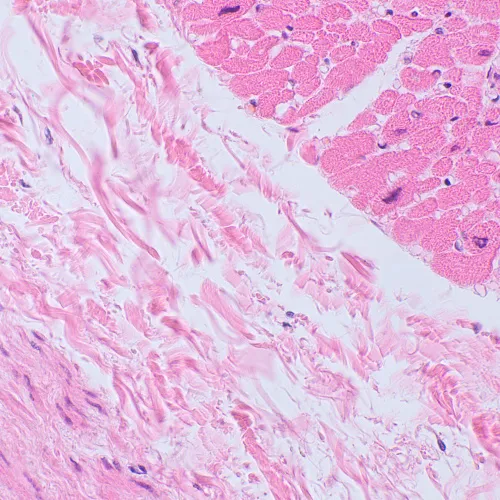

The MAGUS Bio 250BL microscope can be used for laboratory work, scientific research, and student teaching. It is designed to observe thin sections and smears of biological samples in transmitted light. The main method of observation is brightfield, but it is also possible to use darkfield, polarization, and phase contrast techniques (with additional accessories).